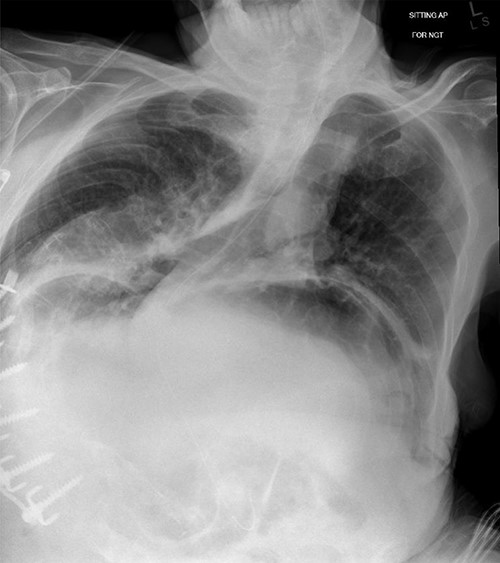

Chest X-ray showing nasogastric decompression of hiatus hernia, along with severe kyphoscoliosis.